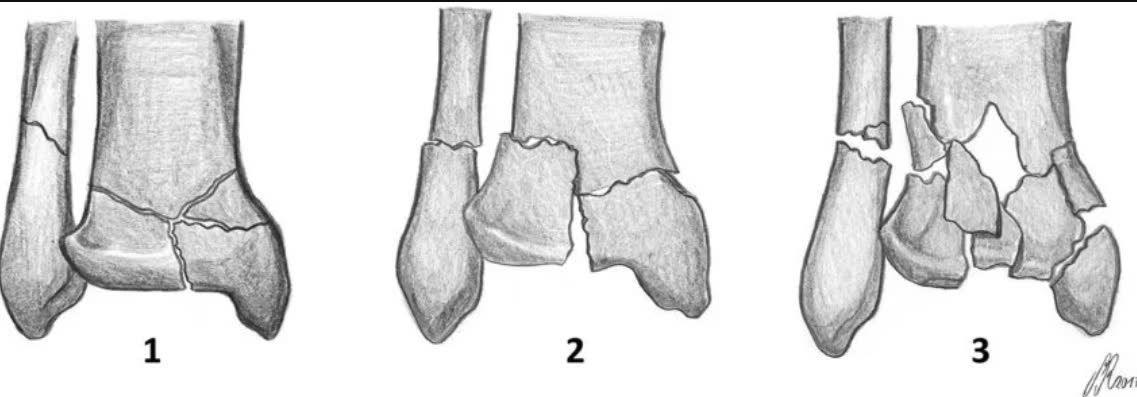

Исторически первая и наиболее простая классификация:

- Тип I — перелом суставной поверхности без смещения, минимальная оскольчатость метафиза

- Тип II — перелом суставной поверхности со смещением, умеренная оскольчатость

- Тип III — оскольчатый перелом суставной поверхности с импакцией, выраженная оскольчатость метафиза

Межнаблюдательская надёжность: хорошая (каппа = 0,61) [Qiu et al., J Foot Ankle Surg, 2020]. Проста и широко распространена, но не определяет хирургический доступ.